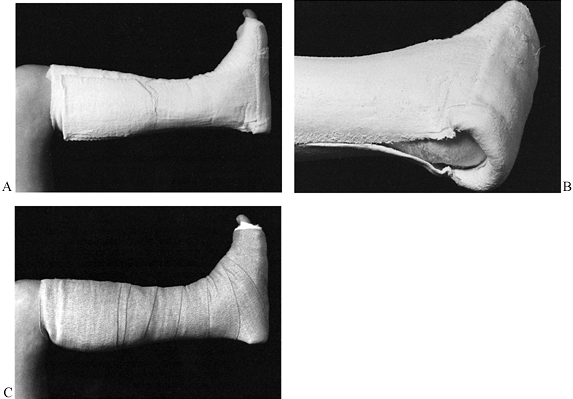

Apply a postoperative dressing and well-padded splints or a Robert-Jones dressing with splints (Fig. 25.12).

Figure 25.12. The postoperative dressing. A:

The dressing is well padded with cotton before plaster application; a

foot plate is made of plaster splints, and a plaster stirrup on both

medial and lateral sides covers the foot plate. The foot plate is then

reversed over the stirrup for further strengthening. B: Close-up view showing the posterior aspect of the plaster. Plaster does not contact the patient’s heel. C:

A light coating of cotton is placed over the plaster to prevent the

compression dressing from sticking to the plaster and becoming

ineffective. Then it is wrapped with an elastic bandage. The foot is in

neutral position.